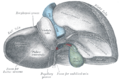

الفصوص

ان التشريح التقليدي للكبد يقسمه الى أربعة فصوص بناء على الشكل الخارجي.

فالرابط المنجلي المشاهد على السطح الأمامي للكبد يقسمه الى فصين يمين ويسار.

بينما يوجد من الخلف فصين أخرين أحدهما موجود بالأعلى ويسمى الذيلي والأخر الاسفل ويسمى الفص الرباعي .caudate and quadrate lobes

ويظهر من الخلف رابطين أخرين هماligamentum teres and ligamentum verosum

وهناك أيضا الشق العرضيtransverse fissure بالخلف والذي يفصل الفصين الذيلي والرباعي عن بعضهما البعض .

Frontal view from Gray's Anatomy(1918)

Back view from Gray's Anatomy(1918)